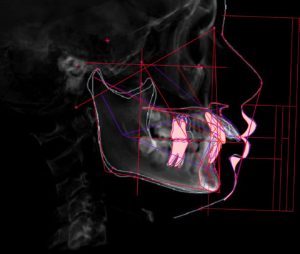

精密検査時に撮影したレントゲン写真をもとに

- 骨の形

- 歯の位置と向き

- 噛み合わせ

- 横顔(口元)

を同時に確認できるようにトレースしたものです。

この画像から読み取れることは

- 上顎第一大臼歯に対して下顎第一大臼歯はほぼ理想的な位置関係に近く

大きなⅡ級、Ⅲ級のズレは認めにくい

- つまりこの症例では骨格的な前後のズレよりも

歯列、歯軸の問題が主因である可能性が高い

- 臼歯関係が安定している=前歯部で問題が解決する可能性が高い

また、CTトレースと側方セファロ分析を組み合わせることで

- 臼歯の咬合関係が治療の基準点として使えるか

- 骨格的なズレが主因なのか、歯列、歯軸の問題なのか

- 前歯を動かすべきか、動かしてはいけないのか

といった判断を、構造と数値に基づいて行います。